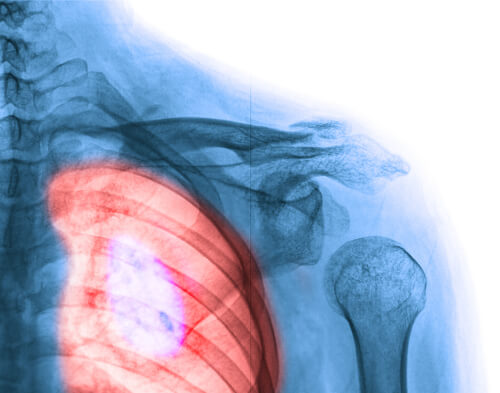

1. Breast Cancer

You probably know someone in your social circle who has breast cancer, or perhaps you’ve even lost a loved one to this terrible disease. But as science advances every day, more and more women are surviving. Breast self-exams and mammograms are key factors in early detection.